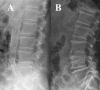

Methods: A total of 47 centres in six European countries participated in this cross-sectional study. Inclusion criteria were age >or=18 years and duration of dialysis >or=3 months. Lateral lumbar radiography of the abdominal aorta was used to determine the overall AAC score, which is related to the severity of calcific deposits at lumbar vertebral segments L1-L4. The reliability of the method was tested by double reading of 64 radiographs (coefficient of correlation 0.9).

Results: A lateral lumbar radiograph was obtained in 933 patients. Calcification (AAC score >or= 1) was present in 81% of the patients; its severity increased significantly from L1 to L4 (P < 0.0001) and affected all of these segments in 51% of patients. Independent predictors for the presence and severity of calcification were age (odds ratio [OR] 1.103/year; P < 0.0001), duration of dialysis (OR 1.110/year; P = 0.002) and history of cardiovascular disease (OR 3.247; P < 0.0001).